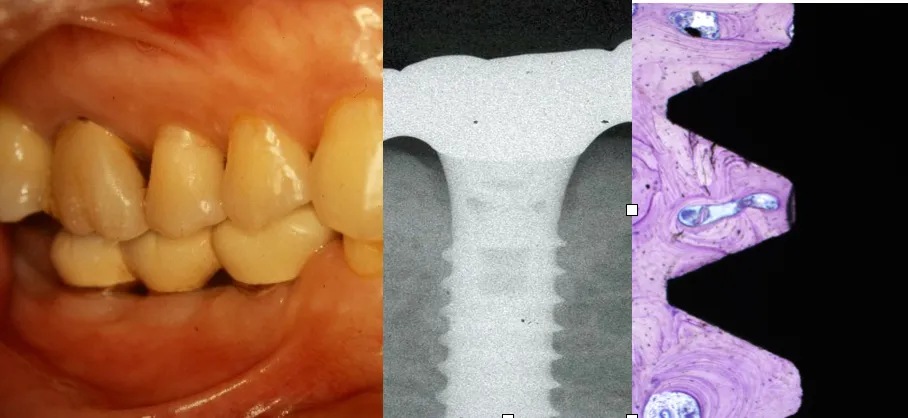

インプラントは、20世紀後半に登場し、今や一般的な治療法として定着しています。しかし、依然としてインプラント治療に対する不安を感じる患者さんが少なくありません。また、医療従事者でさえその導入に臆する現状が続いています。特に、他院でインプラントを受けた患者が新たに診療室を訪れた際、適切なメンテナンスができない恐れもあるため、歯科衛生士に正しい知識が求められています。

画像1

画像2

画像3